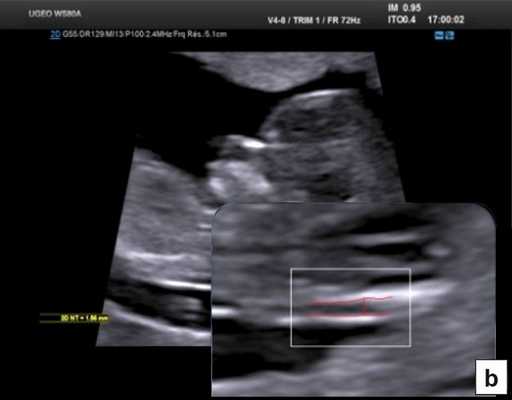

Тем не менее "базовое" УЗИ обычно дополняют исследованием в цветовом энергетическом допплеровском режиме с тщательным анализом для выявления атриовентрикулярного кровотока в четырех камерах сердца (рис. 6a) и в срезе через три сосуда и трахею (рис. 6b). Получив эти срезы, обычно можно успокоить родителей, исключив наличие тяжелых пороков сердца, таких как единственный желудочек, гипоплазия желудочков, полный дефект предсердно-желудочковой перегородки (atrioventricular septal defect - AVSD), атрезия аорты или легочной артерии, а также ряд аномалий расположения артерий.

Рис. 6. Эхокардиография плода на ранних сроках в цветовом энергетическом допплеровском режиме - визуализируются четыре камеры (a) и срез через три сосуда и трахею (b).